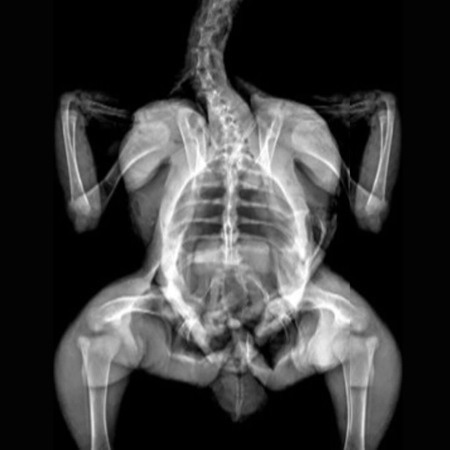

X-Ray Attenuation Image - Rat. Image Credit: Scintica Instrumentation Inc